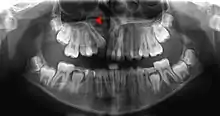

In cases with a single cleft, 35-60% of lateral incisors are congenitally missing,[4] and cannot be relied on for timing. Instead, the eruption of the incisors and first molars is used as a queue to begin assessments. With bilateral cases, the premaxilla must be repositioned before grafting and special consideration must be given. During this time, the orthodontist must be wary of rotating teeth into the cleft site. Last, the size of the patient, defect, and social issues must all be taken into consideration and is best assessed with a CBCT scan as the patient enters the mixed dentition phase of dental development.[5]